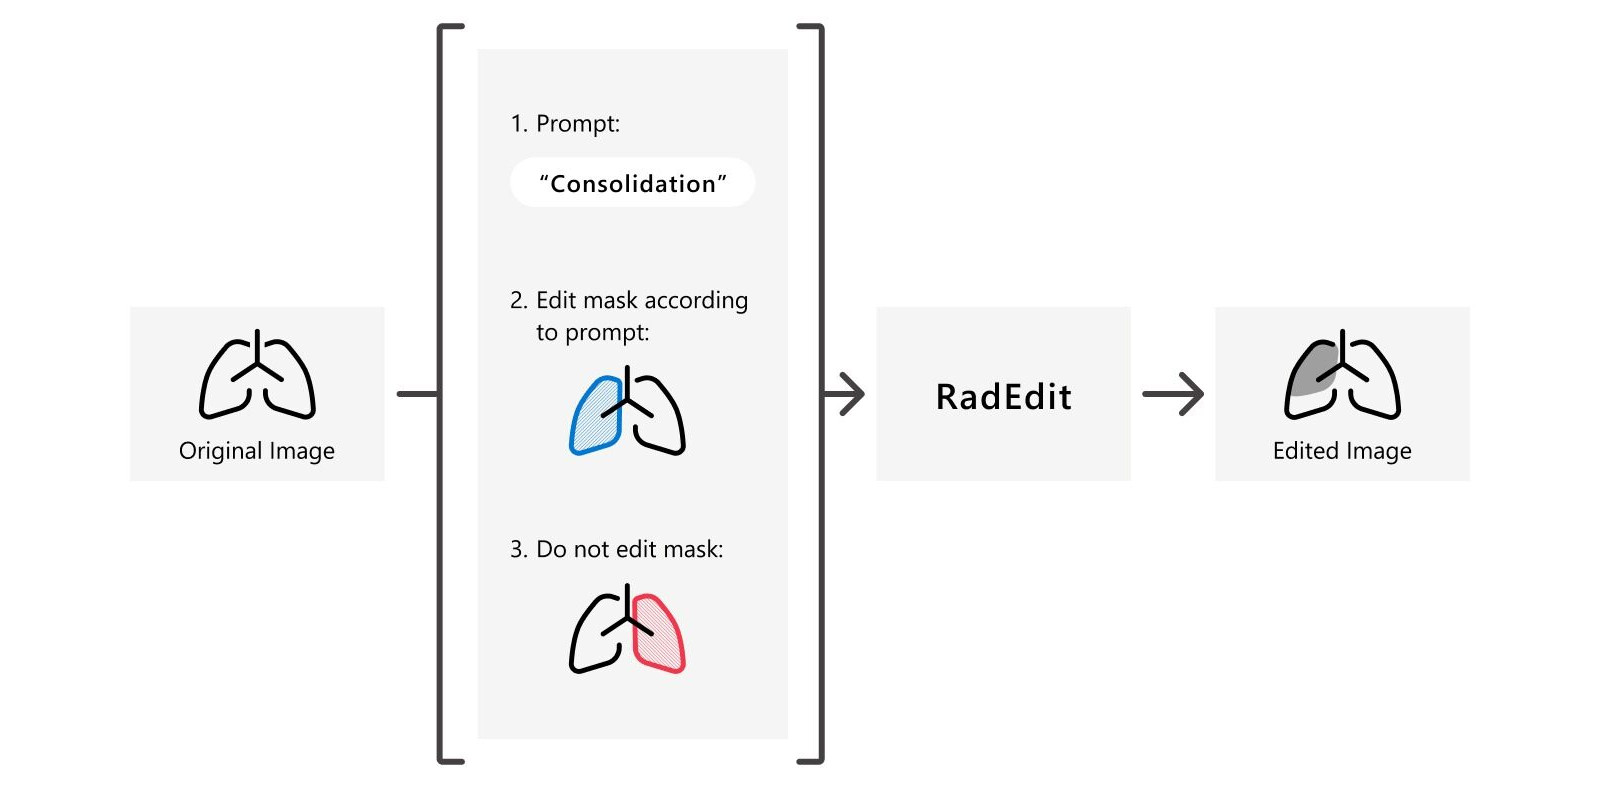

RadEdit is a deep learning approach for stress testing biomedical vision models to discover failure cases. It uses a generative text-to-image model to “edit” chest X-rays by using a text description to add or remove abnormalities from a masked region of the image. These edited images can subsequently be used to test whether existing models (e.g. those for disease classification or anatomy segmentation), perform as expected under these different conditions.

The RadEdit editing pipeline is not applicable to all stress testing scenarios. For example, testing segmentation models’ behaviour to cardiomegaly (enlarged heart) is not possible as this would require segmentation masks to be changed. Other limitations of the editing procedure are discussed in the RadEdit paper.

abstract = {Biomedical imaging datasets are often small and biased, meaning that real-world performance of predictive models can be substantially lower than expected from internal testing. This work proposes using generative image editing to simulate dataset shifts and diagnose failure modes of biomedical vision models; this can be used in advance of deployment to assess readiness, potentially reducing cost and patient harm. Existing editing methods can produce undesirable changes, with spurious correlations learned due to the co-occurrence of disease and treatment interventions, limiting practical applicability. To address this, we train a text-to-image diffusion model on multiple chest X-ray datasets and introduce a new editing method, RadEdit, that uses multiple image masks, if present, to constrain changes and ensure consistency in the edited images, minimising bias. We consider three types of dataset shifts: acquisition shift, manifestation shift, and population shift, and demonstrate that our approach can diagnose failures and quantify model robustness without additional data collection, complementing more qualitative tools for explainable AI.}